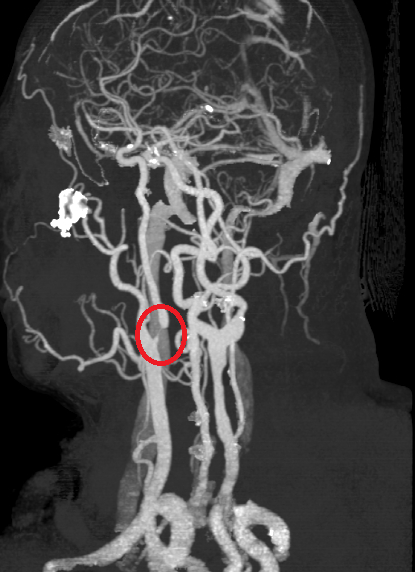

【News586/總社長孫崇文報導】南投一名50歲林姓男子,近期頻繁感到頭暈且左側手腳發麻,隨即前往衛生福利部南投醫院就醫。神經內科鄭耕兆醫師初步進行電腦斷層檢查,雖無立即性的中風徵兆,但憑藉臨床經驗與敏銳覺察,進一步安排頸動脈超音波追蹤。檢查結果顯示,患者內頸動脈已有狹窄問題,院方立刻安排住院,並轉介神經外科陳奕安醫師進行治療。

陳奕安醫師採取內頸動脈血管成形術,透過氣球擴張合併支架置放,成功疏通狹窄血管並改善腦部血流,林先生術後復原狀況優異,目前已順利出院。陳醫師對此強調,頸動脈狹窄是缺血性中風的主因之一,由於早期症狀如頭暈、肢體麻木、甚至短暫視力漆黑等黑矇現象往往轉瞬即逝,極易被病患忽略,若未及時處理,腦部長期缺血將大幅拉高腦中風的發生機率。